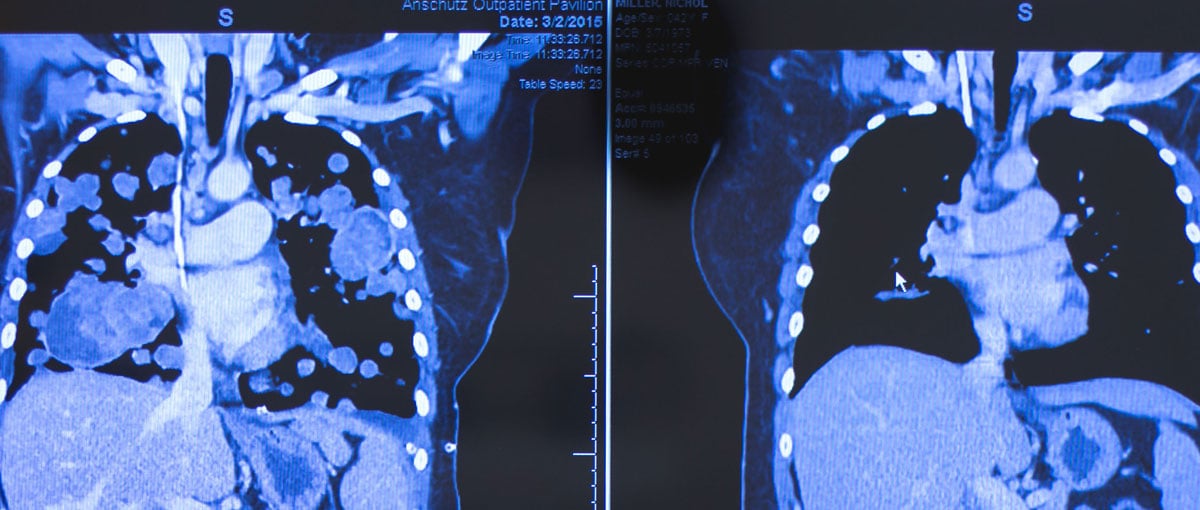

The CAT scan at left was taken March 2, 2015, at the CU Cancer Center when patient Nichol Miller's lungs were covered with tumors. At right is her most recent CAT scan, showing the success of the targeted-therapy drug she is taking as part of a clinical trial.

Tears stream from behind Nichol Miller's glasses as she studies the latest CAT scan of her torso. Where just four months ago tumors covered both lungs, now only a few tiny dots appear.

Miller, a 42-year-old wife and mother of three, has grown accustomed to seeing improvement during her monthly visits to the University of Colorado Cancer Center, but this scan is especially stunning. "'Dramatic' is such an understatement," she says, reaching for a tissue. "There needs to be a bigger word for the transformation of me (in March) and me now. I kind of always sit around waiting for the other shoe to drop — is it going to continue to work? We're in uncharted waters."

After her most recent clinical update, an elated Miller steps into a CU Cancer Center hallway to call family members with the good news. She tells her ecstatic husband about the tumors that are now barely visible on the CAT scan. "They're like specks," she says.